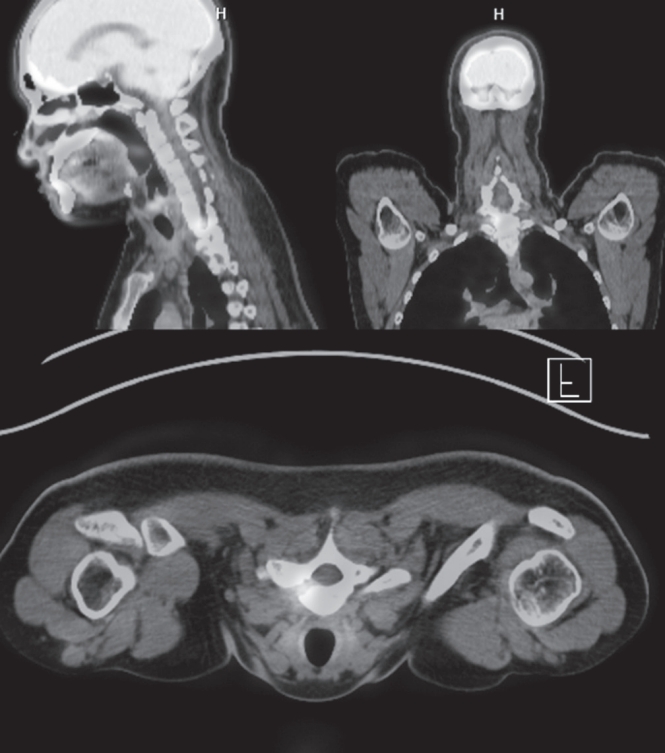

A 24-year-old otherwise healthy male presented with a 4-month history of progressively worsening right-sided upper thoracic and lower cervical pain. The pain was described as deep, dull, and aching in nature, with abrupt nocturnal onset that severely interfered with sleep. He reported frequent nighttime awakenings due to pain, unresponsive to rest or changes in posture. There was no preceding trauma, infection, or history of systemic disease. Initial self-medication with over-the-counter ibuprofen (200 mg, as needed) yielded minimal symptom relief. Upon visiting a local clinic, he was prescribed naproxen 500 mg twice daily for 14 days. As the pain persisted, celecoxib 200 mg twice daily was administered for 3 weeks, followed by etoricoxib 90 mg once daily for an additional 4 weeks. Despite good compliance, the nocturnal pain remained refractory, and his quality of life progressively deteriorated. Neurological examination was unremarkable. There were no signs of motor weakness, sensory changes, hyperreflexia, or upper motor neuron signs. No spinal tenderness or palpable mass was noted. Laboratory investigations, including ESR, CRP, and WBC count, were within normal limits. Given the persistence of symptoms despite aggressive NSAID therapy, advanced imaging was initiated. MRI of the cervicothoracic junction revealed a small lesion involving the superior aspect of the right T1 pedicle. The lesion showed hypointensity on T1-weighted images and central gadolinium enhancement on fat-suppressed T1 post-contrast sequences, surrounded by marrow edema extending into the adjacent vertebral body and lamina. Notably, the lesion appeared to abut the transverse foramen, raising concern for proximity to the vertebral artery. CT imaging demonstrated a well-defined, cortically based radiolucent nidus measuring approximately 1.2 cm, surrounded by dense reactive sclerosis—radiologically characteristic of osteoid osteoma. PET-CT further revealed focally increased FDG uptake in the nidus, indicating active bone turnover and confirming the metabolic activity of the lesion (

Fig. 1). Given the deep anatomical location, adjacent to both the spinal canal and the vertebral artery, wide laminectomy or facetectomy was deemed excessively invasive and potentially morbid. After a multidisciplinary team discussion, the surgical plan involved targeted resection using intraoperative O-arm–based 3D navigation to maximize precision and minimize exposure. Under general anesthesia, the patient was placed in a prone position. A midline posterior cervical incision was made, and subperiosteal dissection was carried out to expose the posterior elements of C7 and T1 on the right side. Intraoperative O-arm 3D imaging was obtained and registered with preoperative CT and MRI data using a StealthStation

Fig. 1.Preoperative PET-CT scan showing increased FDG uptake at the superior margin of the right T1 pedicle. The lesion is metabolically active and consistent with osteoid osteoma.